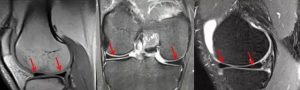

半月板损伤类型

半月板损伤分级

下图III级